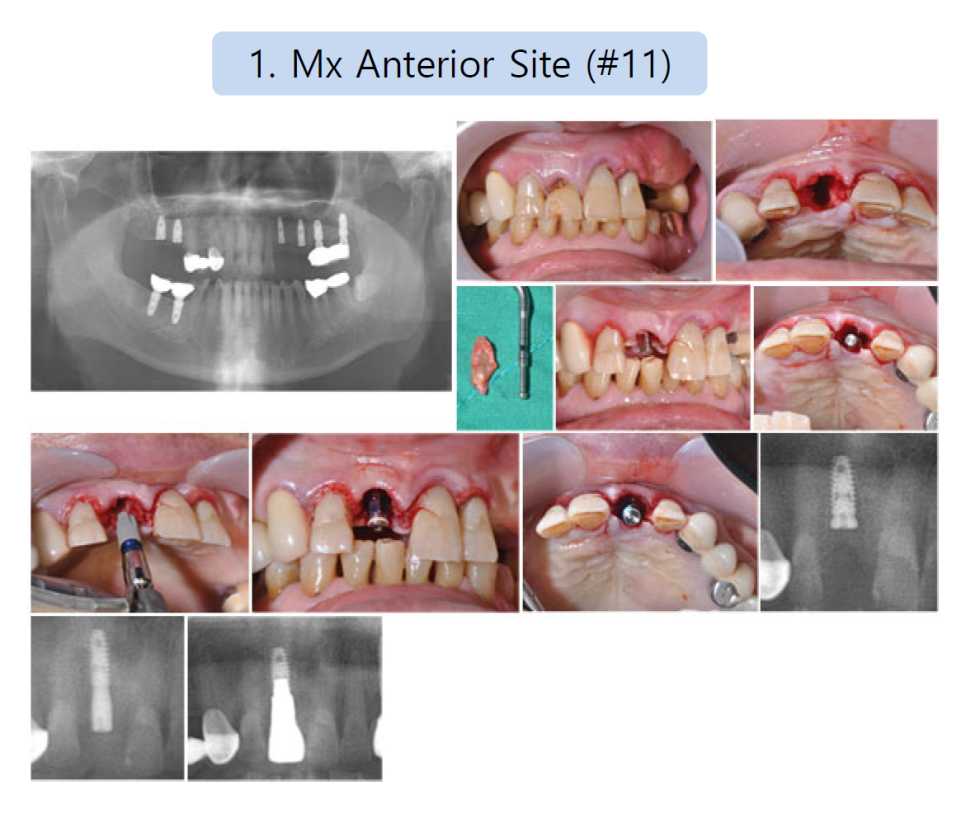

상악 전치부 (#11)

오른쪽 가운데 앞니 치경부에서

큰 충치 소견이 보임.

발치 후 즉시 임플란트 식립을 진행하였음.